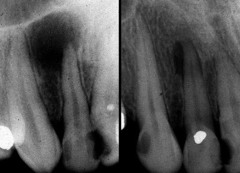

3 stages of Cementoma ("Periapical Cemental Dyplasia")

Front

1. Radiolucent, 2. radiopaque specks, 3. circumscribed area of radiopacity.